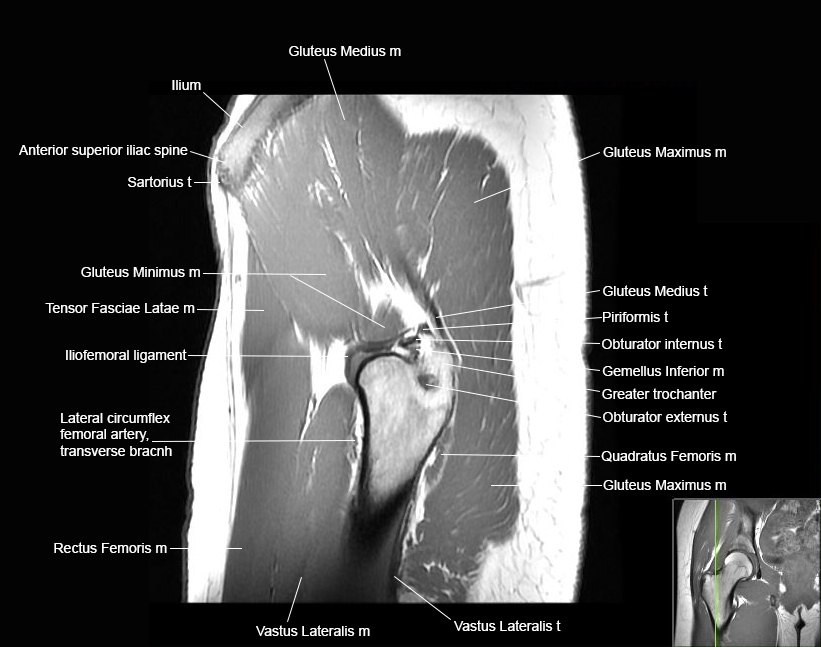

Hip

Basic Hip MRI

MRI Hip Anatomy

Scroll using the mouse wheel or the arrows